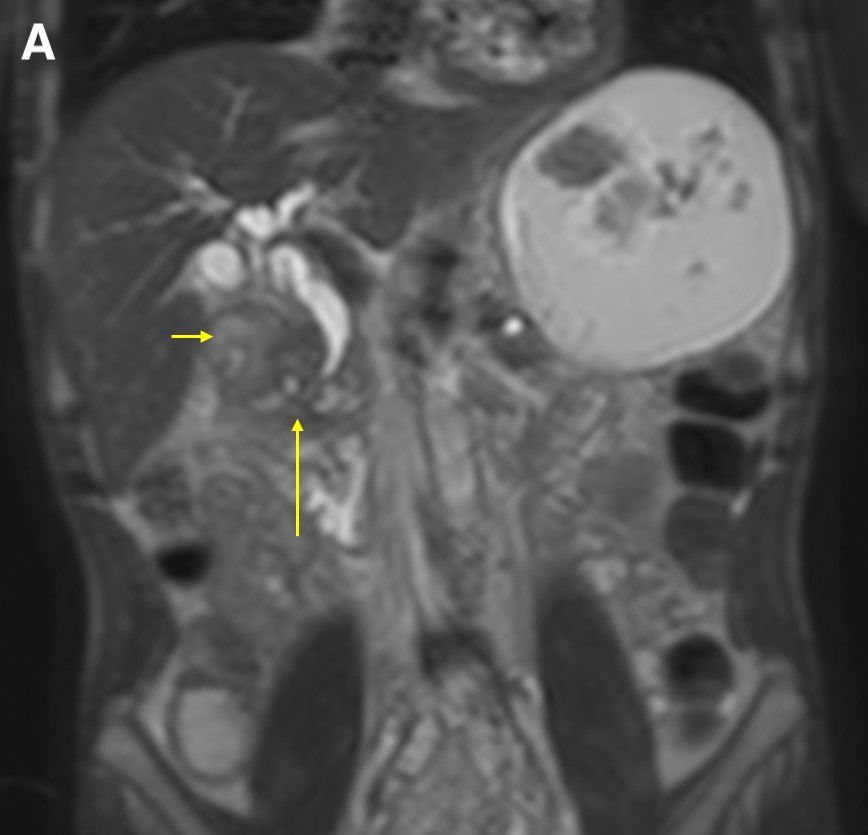

On magnetic resonance imaging (MRI) scans, groove pancreatitis often shows a T1 hypointense “sheet like” mass in the groove space.6 Depending on timing, T2 can demonstrate hypointensity, isointensity, or hyperintensity in this region.1 The initial phase of disease shows T2 hyperintensity, with progression into isointensity or hypointensity caused by fibrosis as the disease course continues.1 Cysts or cystic masses can be seen in the duodenal wall or groove space in T2-weighted imaging, as we saw in our patient (Figure 3).1 Magnetic resonance cholangiopancreatography can be helpful, as it can also demonstrate nonspecific signs such as common bile duct/pancreatic duct dilation.1 Gadolinium-enhanced images show delayed enhancement caused by fibrosis, as we saw in our patient (Figure 4). In one study, approximately 93% of patients showed patchy, late, post-gadolinium enhancement of the pancreas.7 In both the pure and segmental forms of groove pancreatitis, authors of one study found medial wall of the duodenum involvement with mural cysts on T2 weighted imaging.8 In cases of segmental groove pancreatitis, the common bile duct shows gradual tapering, while in cases of malignancy, the duct shows abrupt cutoff, which we saw in our patient (Figure 5).6

Figure 5. A coronal T2WI demonstrated gradual tapering of the dilated common bile duct, with the thickened wall of the duodenum (a, short arrow) and the soft tissue thickening in the groove region around the ampulla (a, long arrow). The maximum-intensity projection reconstruction of the magnetic resonance cholangiopancreatography demonstrated dilated intrahepatic ducts, smooth tapering of the common bile duct (b, short arrow), dilated pancreatic duct, and narrowing of the lumen of the duodenum due to wall thickening (b, long arrow).